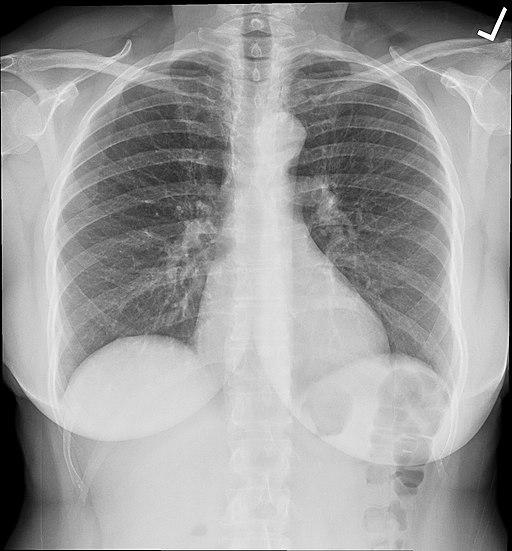

Chest x-rays are the most common imaging study performed; they serve mostly as a screening tool. Could they act as a crystal ball for our future health? A group of researchers using a form of artificial intelligence, a convolutional neural network [1], believes the answer is yes. The study only seeks to prove that chest x-rays contained hidden prognostic information. Let us see what they got.

Here are the graphics and the survival curves.

Chest X-rays were predictive of all-cause mortality, roughly 70% of the time (A), slightly lower in the group of dedicated smokers (B). More importantly, the addition of the chest x-ray risk analysis by the neural net improved the predictive value from 50% when based solely on the radiologist’s findings — translated, while a radiologist’s findings resulted in a coin flip chance of predicting mortality, the hidden in plain sight visualizations by the neural network increased performance to 70%.

The artificial intelligence was able to stratify the risk of dying better than a radiologist looking at one film, but as the researchers state, the “prognostic value was complementary to the radiologists’ diagnostic findings and standard risk factors…. Our data suggest that deep learning systems can extract prognostic information from existing diagnostic studies.” They suggest that we consider these images as more of a complete summary of our current health than as a screening tool for respiratory disease.